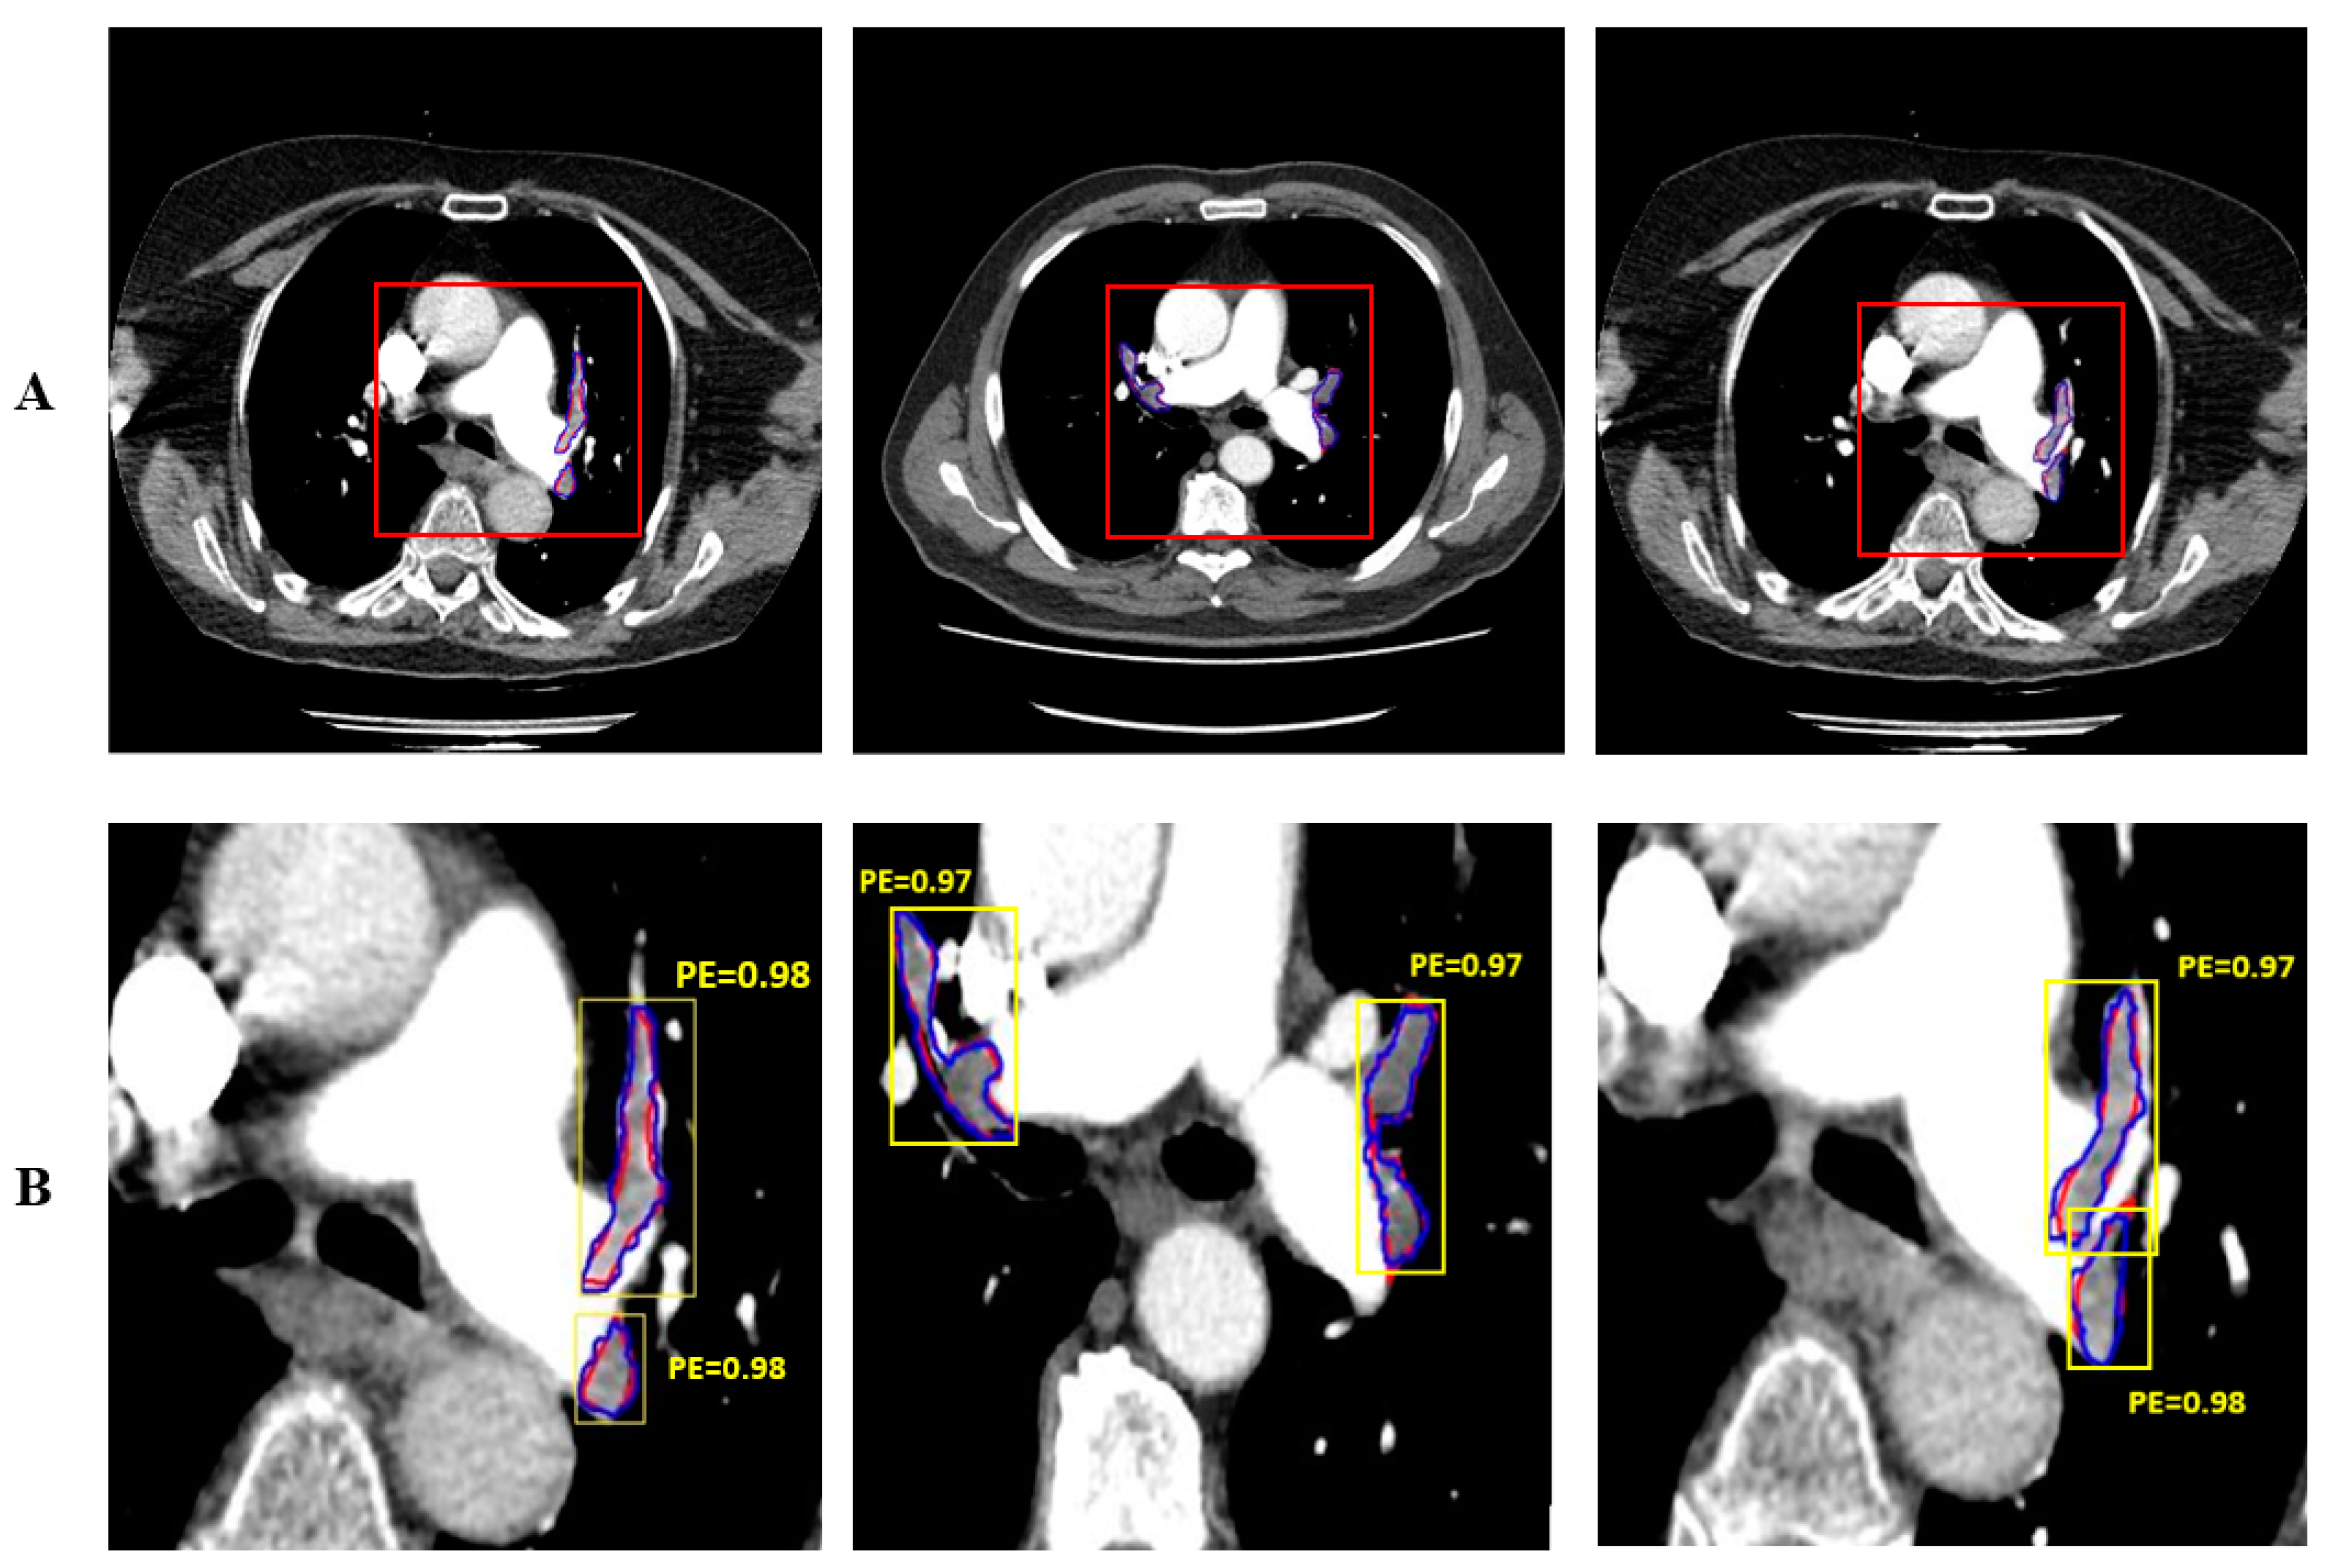

In this study, thorax CT images of 50 patients with pulmonary embolism were used. Images containing a total of 430 pulmonary embolisms were created by taking the sections in which the pulmonary embolism was seen from these images. The study was carried out in four stages: data augmentation, preprocessing, PE segmentation, and performance evaluation. Preprocessed images were used as input to the Mask R-CNN network. Images of 36 patients (1505) were used for training, and images of 14 patients (645) were used for testing. Feature extraction for PE detection was performed with the ResNet50 convolutional neural network pre-trained with the COCO dataset. Both hold-out validation (70% train 30% test) and 10-fold cross-validation were used for performance evaluation. Figure 6 shows the automatically and manually segmented PE’s. The PE manually segmented by the expert doctor is shown in red and the PE automatically segmented by the proposed system is shown in blue. Mask R-CNN performs both detection and segmentation. The detection of PE is shown with yellow bounding box.

Figure 6. Automatic and manual segmentation of PE and detection performance, A. Original Size images, B. Zoomed images.